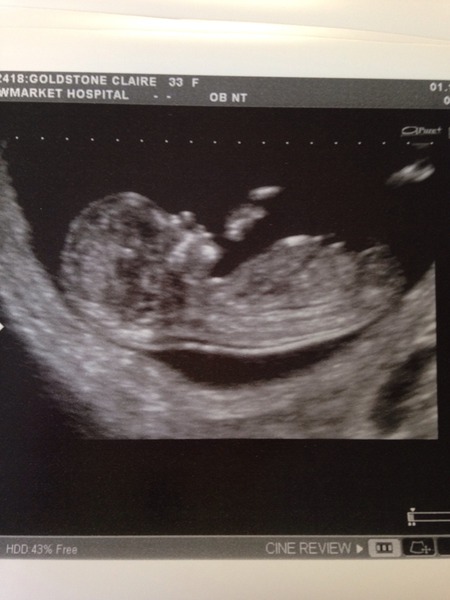

A very healthy little baby now due 6th April. Thank you all for your thoughts :)

Wow, excellent news and picture Cinnamon :)

Ah what a gorgeous little bean!

Gorgeous scan cinnamon - feel quite emotional seeing that little cinnamon all cosy